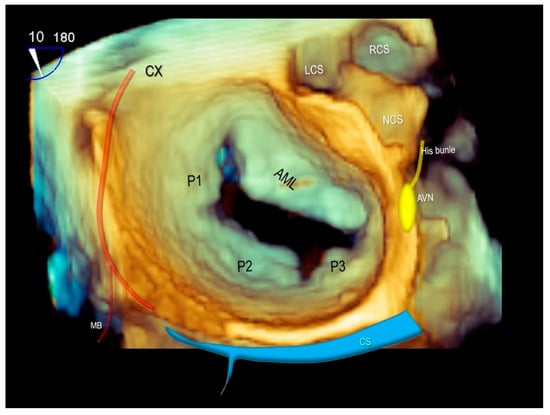

Of note, both the circumflex coronary artery and the coronary sinus are closely related to the posterior mitral valve annulus and can be susceptible to perioperative injury. Furthermore, the atrio-ventricular node is above to the posteromedial commissure of the mitral valve with a potential risk of damage to the atrio-ventricular conduction (Figure 11) [45,46].

Figure 11.

Three-dimensional TEE surgical view of mitral valve showing the anatomical relationships of mitral valve with the circumflex coronary artery (CX), the coronary sinus (CS) and the atrio-ventricular node (AVN). AML = anterior mitral leaflet, P1–P2–P3 = scallops of posterior mitral leaflet, LCS = left coronary sinus, RCS = right coronary sinus, NCS = non-coronary sinus, MB = marginal branch of CX.